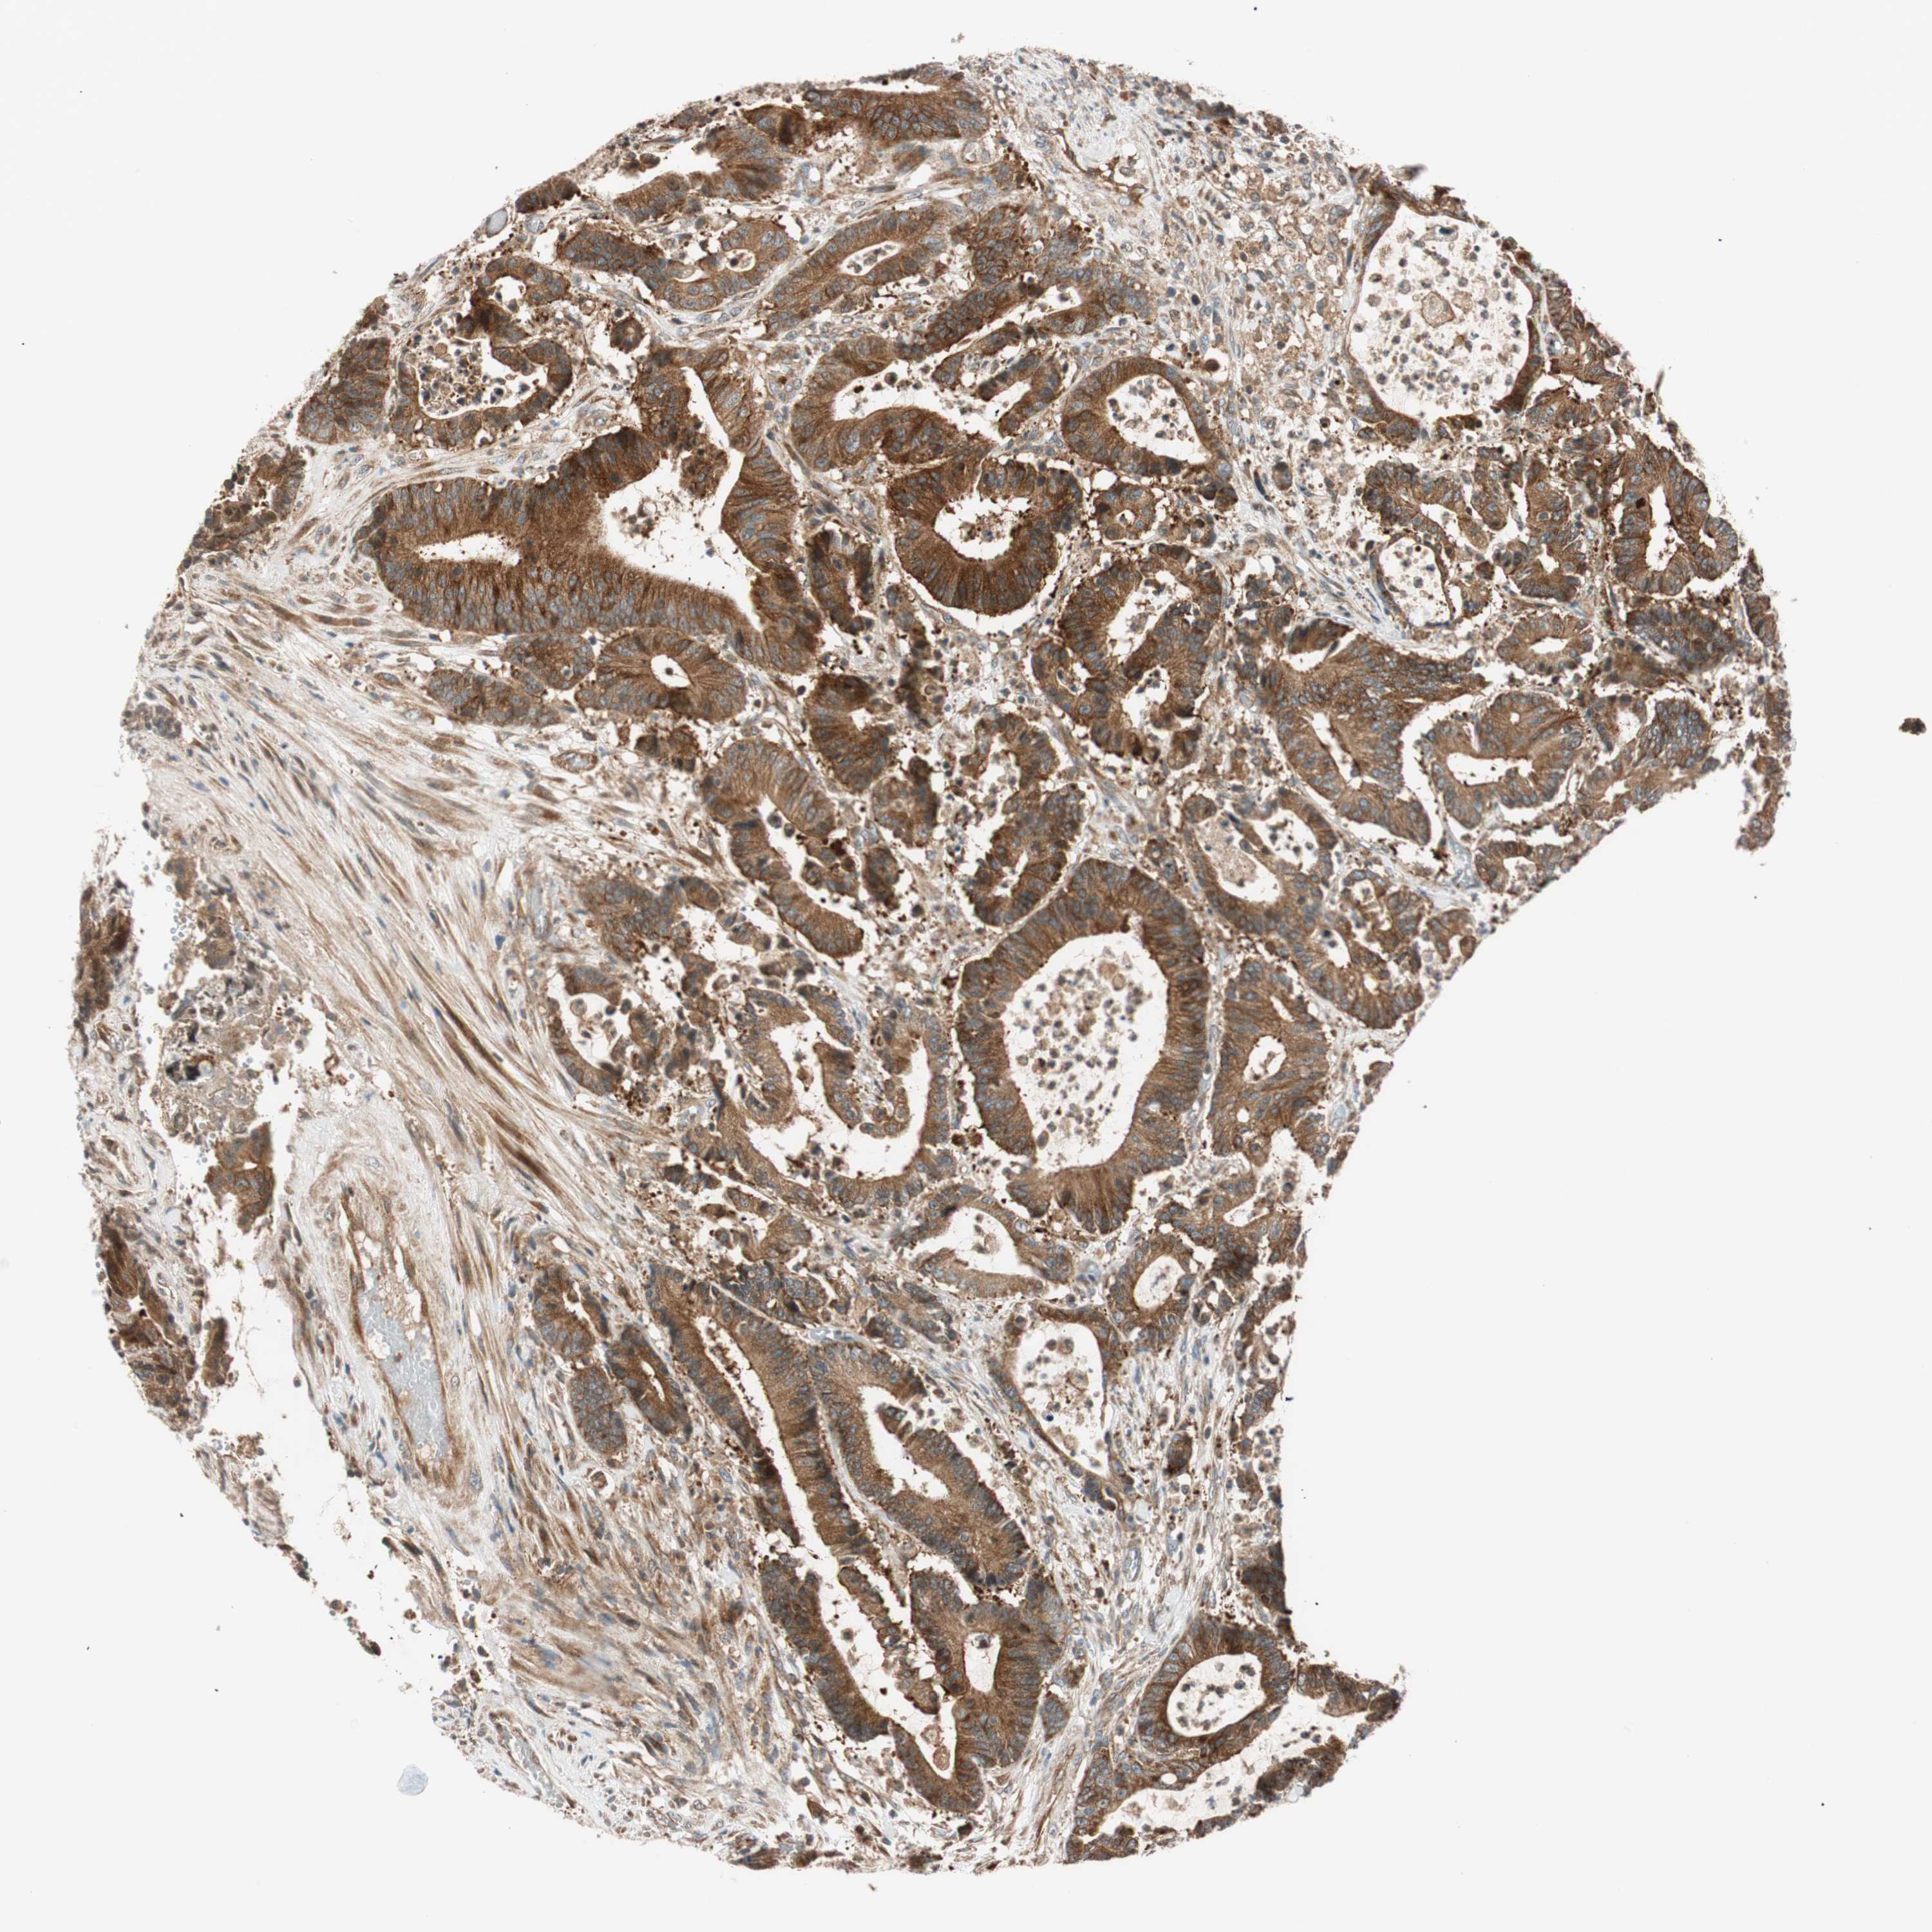

CANCER COLORECTAL CANCER Show tissue menu

Colorectal cancer

Human cancer

Colon adenocarcinoma